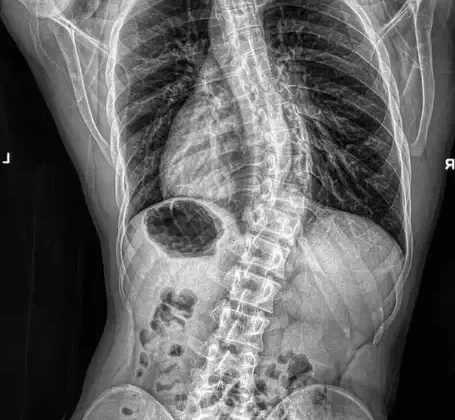

يقاس الانحناء عادة بما يُعرف بـ زاوية كوب (Cobb Angle)، وهي المعيار الطبي لتحديد شدة الحالة.

كلما زادت زاوية الانحناء، زادت شدة الحالة. لكن ليس كل انحناء يتطور بنفس السرعة، فمعدل التغير يختلف من شخص لآخر.